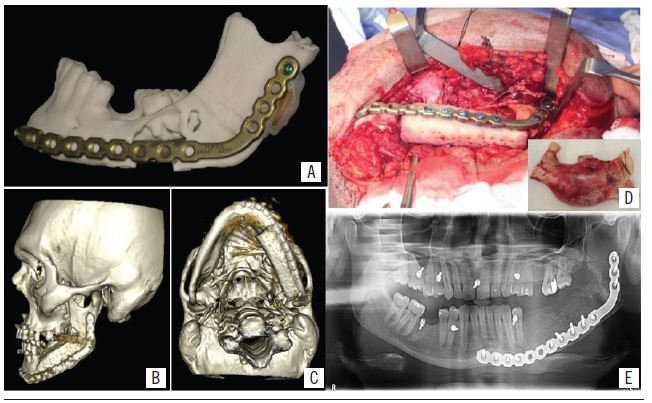

Given these findings, the following were ordered: multislice computed tomography (CT) for a more detailed evaluation of the lesion (Figure 1D), confection of a prototype biomodel for surgical planning, as well as laboratory tests and surgical risk evaluation for the conduction of lesion resection and immediate reconstruction.

Tumor mass excision was performed with a safe margin, anterior and posterior to the lesion margins, measuring 1 cm, followed by the insertion of a mandible reconstruction plate of the 2.4-mm system; this one was pre-molded at a prototyped biomodel. Along with this procedure, the orthopedic team of Hospital Universitário Onofre Lopes removed the graft from the iliac crest region so that after insertion of the reconstruction plate, the graft was prepared, its adaptation and fixation in the resected region, aided by the 2.4-mm screw system and a mechanotherapy was applied with rubber bands (Figure 3). Finally, insertion was concluded with suture of access sites and application of pressure dressings.